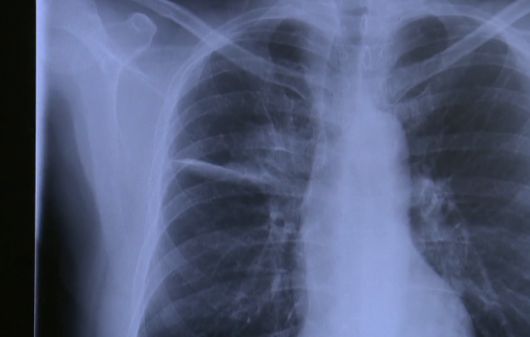

그러나 2022년 6월 그는 "헬스장에서 운동 중 쌕쌕거리는 소리가 났다. 이때 뭔가 잘못된 것을 느꼈다"며 호흡 이상과 어깨 통증을 느껴 검사를 받았다. 이어 컴퓨터단층촬영(CT)을 통해 양쪽폐와 뼈에 침전물이 쌓여있음을 확인했고 4기 진행성 비소세포폐암 진단을 받았다. 직접 본인의 사무실 컴퓨터에서 흉부 엑스레이를 확인한 그는 즉시 암임을 직감했다고 회상했다. 이후 표적치료제와 화학·방사선 치료를 병행했으며 정기적인 검진과 함께 ‘90일 챌린지’를 통해 운동·예술 등 새로운 활동에 도전하며 투병 생활을 이어가고 있다.